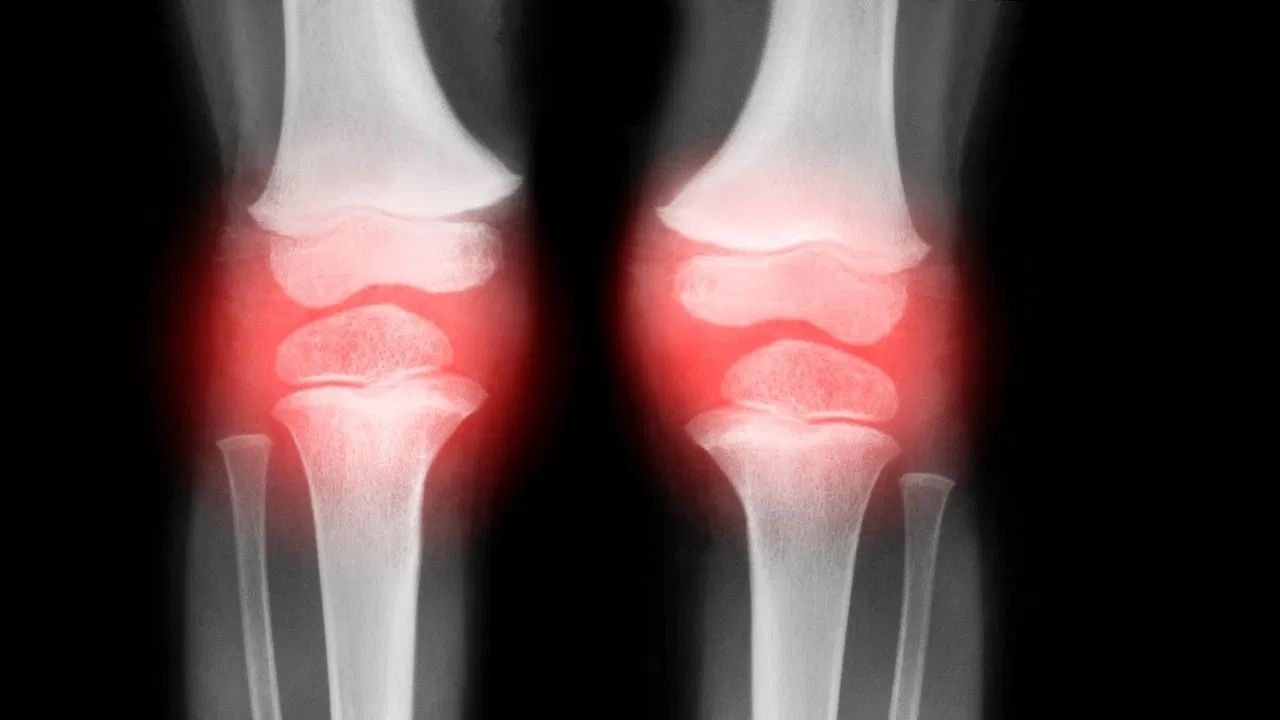

ਹੱਡੀਆਂ ਨਾ ਸਿਰਫ਼ ਸਰੀਰ ਨੂੰ ਆਕਾਰ ਅਤੇ ਸਹਾਰਾ ਦਿੰਦੀਆਂ ਹਨ, ਸਗੋਂ ਸਾਡੇ ਰੋਜ਼ਾਨਾ ਜੀਵਨ ਦੇ ਹਰ ਛੋਟੇ-ਵੱਡੇ ਕੰਮ ਨੂੰ ਵੀ ਸੰਭਵ ਬਣਾਉਂਦੀਆਂ ਹਨ। ਮਜ਼ਬੂਤ ਹੱਡੀਆਂ ਸਰੀਰ ਵਿੱਚ ਕੈਲਸ਼ੀਅਮ ਸੰਤੁਲਨ ਬਣਾਈ ਰੱਖਦੀਆਂ ਹਨ, ਜੋ ਮਾਸਪੇਸ਼ੀਆਂ ਨੂੰ ਊਰਜਾ ਪ੍ਰਦਾਨ ਕਰਦੀਆਂ ਹਨ ਅਤੇ ਦੰਦਾਂ ਨੂੰ ਸਿਹਤਮੰਦ ਰੱਖਦੀਆਂ ਹਨ। ਉਮਰ ਦੇ ਨਾਲ ਹੱਡੀਆਂ ਦੀ ਘਣਤਾ ਘੱਟਦੀ ਜਾਂਦੀ ਹੈ, ਇਸ ਲਈ ਮਜ਼ਬੂਤ ਹੱਡੀਆਂ ਦਾ ਹੋਣਾ ਖਾਸ ਮਹੱਤਵ ਰੱਖਦਾ ਹੈ। ਮਜ਼ਬੂਤ ਹੱਡੀਆਂ ਹੋਣ ਨਾਲ ਸਰੀਰ ਦੀ ਸਥਿਤੀ ਵਿੱਚ ਸੁਧਾਰ ਹੁੰਦਾ ਹੈ ਥਕਾਵਟ ਘੱਟਦੀ ਹੈ ਅਤੇ ਭਵਿੱਖ ਵਿੱਚ ਹੋਣ ਵਾਲੀਆਂ ਓਸਟੀਓਪੋਰੋਸਿਸ ਵਰਗੀਆਂ ਸਮੱਸਿਆਵਾਂ ਨੂੰ ਰੋਕਣ ਵਿੱਚ ਮਦਦ ਮਿਲਦੀ ਹੈ।

ਕਮਜ਼ੋਰ ਹੱਡੀਆਂ ਸਿਰਫ਼ ਇੱਕ ਸਧਾਰਨ ਸਿਹਤ ਸਮੱਸਿਆ ਨਹੀਂ ਹਨ। ਇਹ ਕਈ ਤਰ੍ਹਾਂ ਦੀਆਂ ਸਿਹਤ ਸਮੱਸਿਆਵਾਂ ਦਾ ਕਾਰਨ ਵੀ ਬਣ ਸਕਦੀਆਂ ਹਨ। ਪਹਿਲਾਂ, ਕਮਜ਼ੋਰ ਹੱਡੀਆਂ ਫ੍ਰੈਕਚਰ ਦੇ ਜੋਖਮ ਨੂੰ ਵਧਾਉਂਦੀਆਂ ਹਨ। ਥੋੜ੍ਹੀ ਜਿਹੀ ਡਿੱਗਣ ਨਾਲ ਵੀ ਹੱਡੀ ਟੁੱਟ ਸਕਦੀ ਹੈ, ਜਿਸ ਨਾਲ ਲੰਬੇ ਸਮੇਂ ਤੱਕ ਬਿਸਤਰੇ ‘ਤੇ ਆਰਾਮ ਕਰਨਾ ਪੈ ਸਕਦਾ ਹੈ।

ਇਸ ਤੋਂ ਇਲਾਵਾ, ਕਮਜ਼ੋਰੀ ਜੋੜਾਂ ਵਿੱਚ ਦਰਦ, ਪਿੱਠ ਅਤੇ ਕਮਰ ਦੀ ਕਠੋਰਤਾ, ਗਤੀਸ਼ੀਲਤਾ ਦੀਆਂ ਸਮੱਸਿਆਵਾਂ ਅਤੇ ਸਹਿਣਸ਼ੀਲਤਾ ਵਿੱਚ ਕਮੀ ਦਾ ਕਾਰਨ ਬਣ ਸਕਦੀ ਹੈ। ਓਸਟੀਓਪੋਰੋਸਿਸ, ਕੈਲਸ਼ੀਅਮ ਦੀ ਘਾਟ, ਅਤੇ ਵਿਟਾਮਿਨ ਡੀ ਦੀ ਕਮੀ ਵੀ ਯੋਗਦਾਨ ਪਾਉਣ ਵਾਲੇ ਕਾਰਕ ਹਨ। ਕਮਜ਼ੋਰ ਹੱਡੀਆਂ ਬਜ਼ੁਰਗਾਂ ਵਿੱਚ ਸੰਤੁਲਨ ਨੂੰ ਵਿਗਾੜਦੀਆਂ ਹਨ, ਜਿਸ ਨਾਲ ਡਿੱਗਣ ਦਾ ਜੋਖਮ ਵੱਧ ਜਾਂਦਾ ਹੈ।